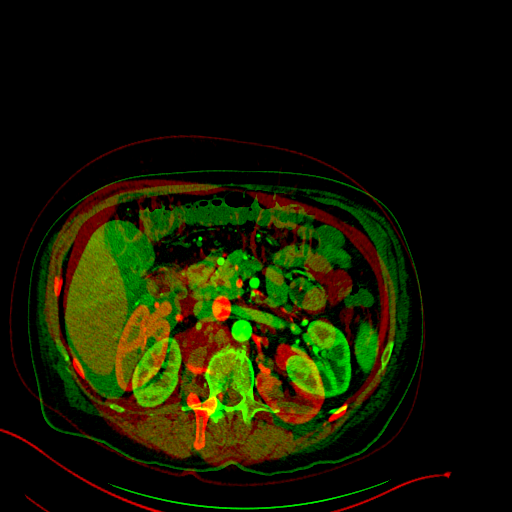

Normalisation of medical images is a important step for data acquisition

Before

linear registration :

After

Non Linear registration

Diffeomorphic matching => Keeps the Topology